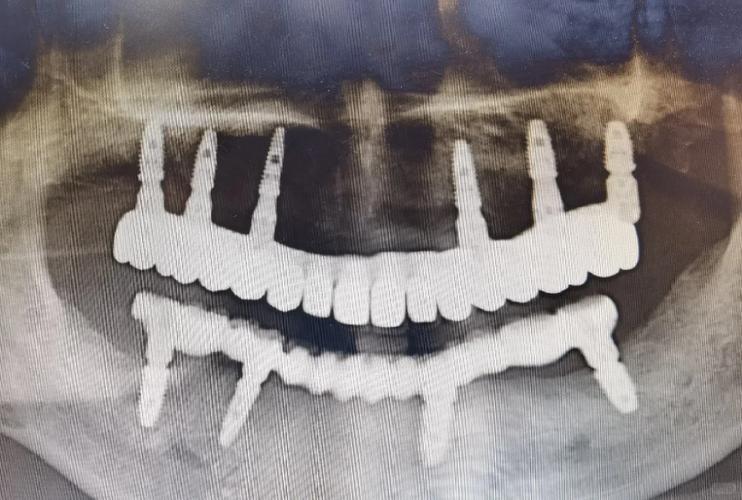

全口种植牙的目标是在上下颌骨中植入种植体,以此为基础安装固定或可摘的修复体,恢复牙齿功能与美观,杭州主流采用的技术方案包括:

- 原理: 这是最主流的全口种植方案之一,通过在上下颌牙槽骨中植入4颗(All-on-4)或6颗(All-on-6) 特殊设计的种植体(通常后牙区倾斜植入,避开上颌窦、下牙槽神经管等解剖结构),利用种植体之间的角度和支撑力,安装一个整排的、固定的牙桥(通常12-14颗牙)。

- 原理: 在上下颌分别植入6-8颗或更多种植体,然后在种植体上安装一个固定的全瓷或烤瓷牙桥。

(图片来源网络,侵删)- 原理: 在拔除残根/残冠的同时或极短时间内植入种植体,并在满足严格条件(如初期稳定性好、无急性感染、咬合力控制好)的情况下,当天或短期内(1-3天) 安装临时修复体。

(图片来源网络,侵删)如前所述,All-on-4/6结合即刻负重是杭州全口种植的一大亮点,能满足患者快速恢复美观和功能的需求。